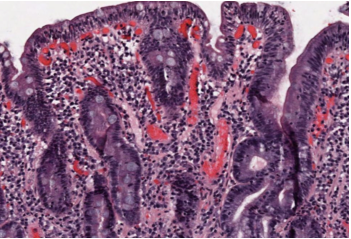

27 year-old male has a history of longstanding abdominal pain and diarrhea. What is the histologic finding below indicative of?

Crohn Disease non-caseating granuloma

Disordered immune response to intestinal bacteria:

Extraintestinal manifestations:

- migratory polyarthritis, erythema nodosum, ankylosing spondylitis, uveitis, Oxalate kidney stones (low calcium reabsorption–> oxalate crystal formation)

Labs:

- HLA-DR1, NOD2 (epithelial cells, leukocytes oversecrete NF-kappaB)